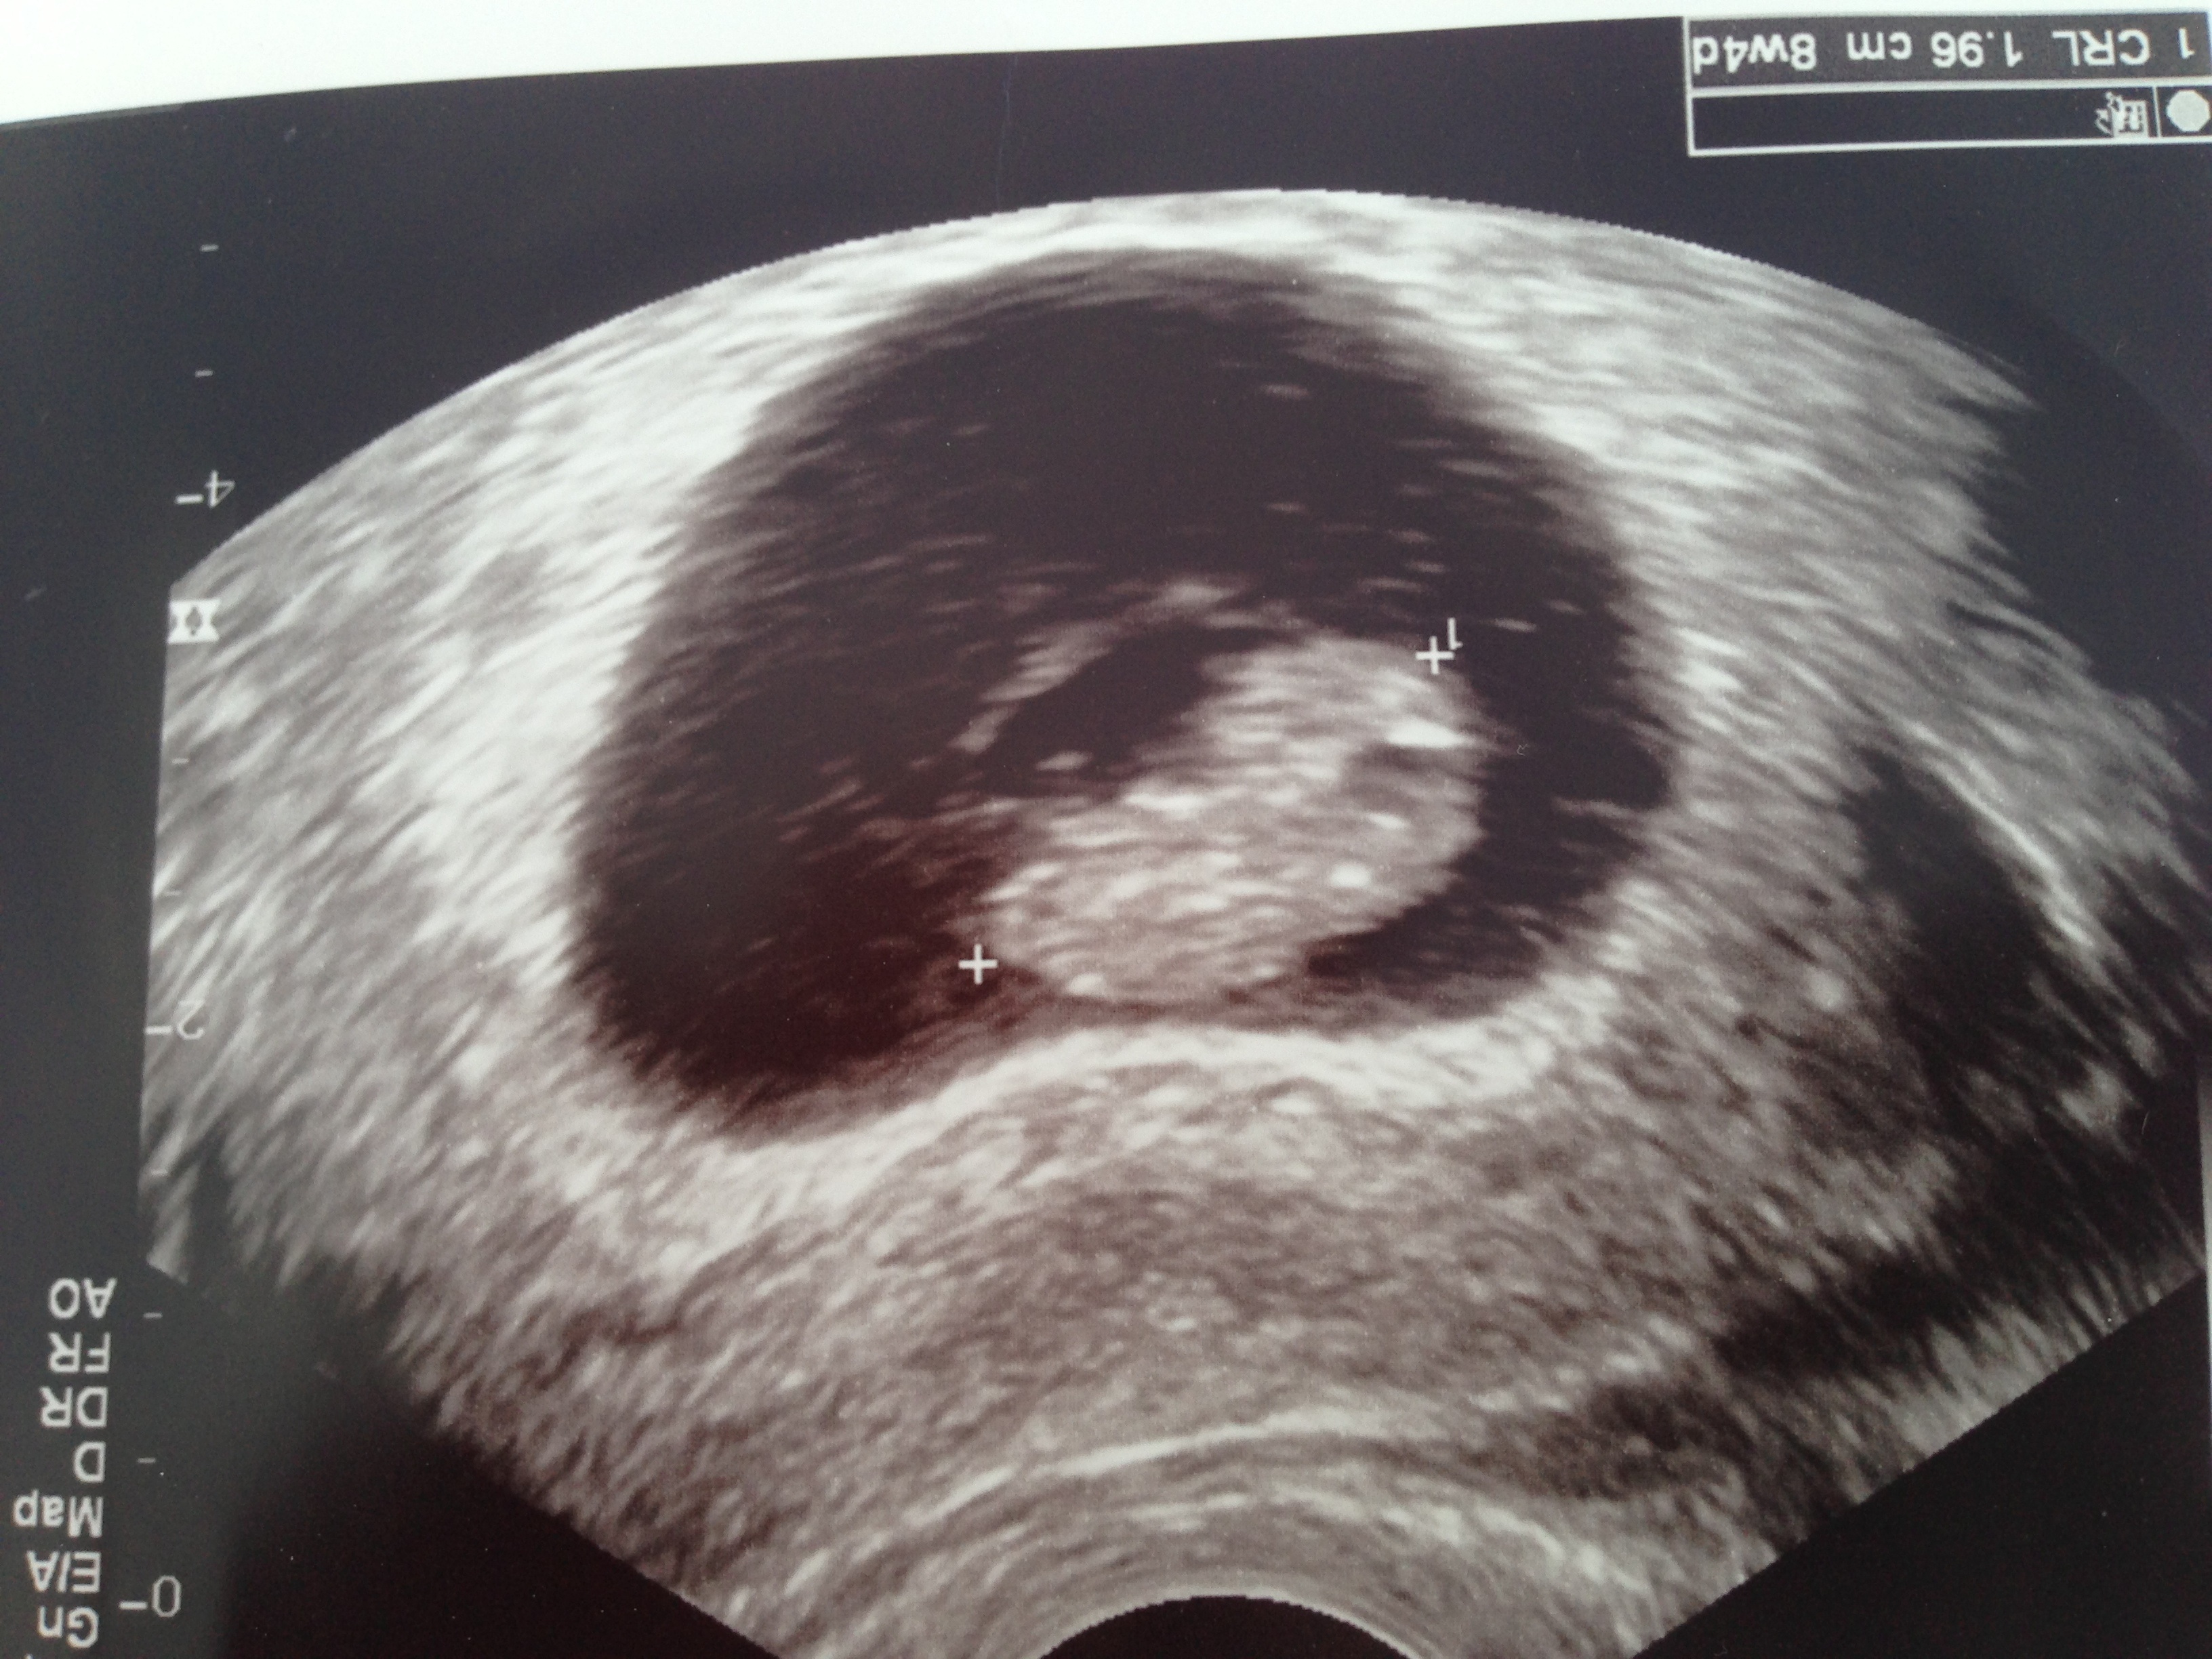

It breaks my heart that there have been so many losses today. Sending love to everyone. Here's our pic from last week at 6w3d. Can't wait to see the changes this week!

Here's our pic from last week at 6w3d. Can't wait to see the changes this week!